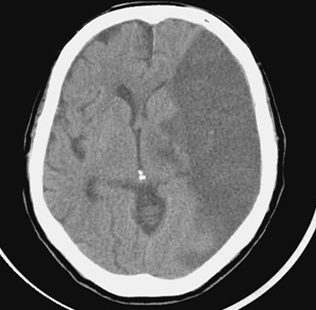

뇌경색이란 무엇인가요?

뇌경색은 뇌의 특정 부위에 혈액이 공급되지 않아 발생하는 문제입니다. 주로 혈관이 막히거나 좁아져 혈액이 제대로 흐르지 않을 때 발생하죠. 전 세계적으로 많은 사람들이 이 질환으로 고통받고 있으며, 특히 노인층에서 빈번하게 발생합니다. 뇌경색을 예방하고 조기에 발견하는 것이 중요한 이유는 이 질환이 뇌에 큰 손상을 줄 수 있기 때문입니다.